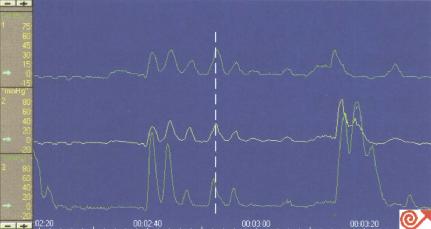

2 嘱患者做数次(如:10次)湿咽,检测吞咽后的LES松驰(图8.31)。因检测过程中患者常取平卧位,可用10~50ml注射器装满室温水,每次向患者口腔内注入温水5~10ml,之后嘱患者吞咽进行检测。检测过程中两次湿咽间应停顿至少20~30秒,并于每次湿咽时在计算机屏幕上做好标记。

图8.31吞咽时LES松弛。游标指示咽部收缩时LES即开

始松弛,白色水平线表示LES松弛持续时间。

(a)如吞咽时LES完全松驰,则压力降至接近胃内压基线水平

(b)LES完全性松驰的定义为:松驰率大于90%(残余压低于5mmHg)